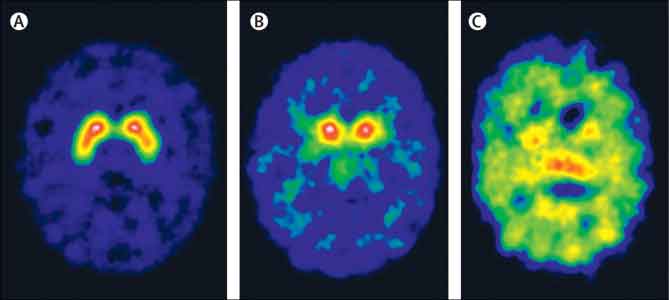

Scienziati americani hanno identificato il ‘centralino’ del cervello che filtra gli stimoli che ci bombardano quotidianamente e selezione quelli che sono piu’ importanti per la nostra sopravvivenza. Come si legge su ‘Science’, un’area del nostro cervello, la pulvinare, regolerebbe i segnali fra gruppi di cellule cerebrali in modo da far concentrare il cervello su oggetti e persone che necessitano della nostra attenzione. Come una sorta di centralinista, il pulvinare assicura che aree distinte della corteccia visiva, che elabora le informazioni visive, si mettano in comunicazione a proposito delle medesime informazioni esterne, si legge nello studio della Princeton University.

Senza la supervisione del pulvinare, una osservazione come quella che si sta avvicinando un autobus potrebbe perdersi in un groviglio di altri stimoli. “Un problema fondamentale per il cervello e’ che ci sono troppe informazioni che provengono dal nostro ambiente naturale per essere tutte trasformate contemporaneamente in dettagli”, ha spiegato Yuri Saalmann, che ha condotto lo studio. “Il cervello si concentra allora selettivamente sulle persone e gli oggetti piu’ rilevanti per il nostro comportamento al momento, e filtra tutto il resto”, ha concluso. (AGI)